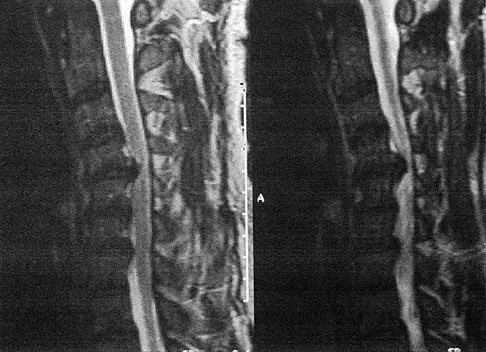

A 51-year-old man sustained an open fracture of his tibia in Korea 42 years ago. An infection developed and it was resolved with surgical treatment. For the past 6 months, an ulcer with mild drainage has developed over the medial tibia. The ulcer is small and there is minimal erythema at the ulcer site. A radiograph and MRI scan are shown in Figures 43a and Figure 43b. Initial cultures show Staphylococcus aureus susceptible to the most appropriate antibiotics. Laboratory studies show an erythrocyte sedimentation rate of 70 mm/h. What is the most appropriate surgical treatment at this time?

Explanation